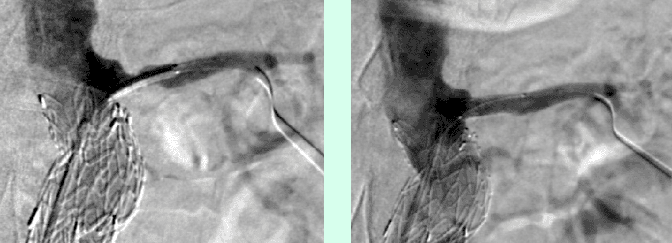

Alternativ zur offenen chirurgischen Therapie eines Aortenaneurysmas besteht die Möglichkeit einer endovaskulären Aneurysmaausschaltung mittels eines Stentgrafts (gewebeummanteltes Metallgittergeflecht). Voraussetzung für die endovaskuläre Therapie ist jedoch eine anatomische Eignung, welche eine ausreichende Weite der Beckengefäße und nötige Verankerungszonen für den Stentgraft mit sich bringt. Die Stentgraft Implantation wird von Interventionellen Radiologen in Zusammenarbeit mit Anästhesist:innen und Gefäßchirurg:innen durchgeführt. Der Eingriff erfolgt unter Spinalanästhesie oder einer Allgemeinnarkose. Der Zugang zum Aneurysma wird üblicherweise durch einen kurzen Schnitt in der Leiste geschaffen. Zur Darstellung des Aneurysmas wird zuerst eine Angiographie der Bauchaorta durchgeführt (Abb.2). Folglich wird unter Röntgendurchleuchtung der Stentgraft über einen Führungsdraht in die Bauchaorta eingebracht und unterhalb der Nierenarterien verankert. Eine Kontrollangiographie nach Stentgraft-Implantation wird zum Nachweis eines guten Ausschlusses des Aneurysmas durchgeführt (Abb.3).

Bei elektiver chirurgischer Sanierung von Descendensaneurysmen wird die 30-Tages-Mortalität mit 5–13% angegeben. Weitere postoperative Komplikationen sind respiratorische Probleme, bis zu 33% neurologische Defizite und renale Insuffizienz bis zu 8%. Die endovaskuläre Stentgraft-Therapie hat deutlich geringere Mortalitäts- und Komplikationsraten und hat als Alternativmethode eine große Bedeutung in der Behandlung von Aneurysmen in der Aorta descendens und des Aortenbogens erlangt. Bei Beteiligung des Aortenbogens sind vorausgehende chirurgische Umbauten von Aortenbogenästen erforderlich, um eine Stentgraft Verankerung zu ermöglichen. Abbildung 4a zeigt ein Aneurysma mit Beteiligung des  Aortenbogens und Abgang der linken Halsschlagader (Arteria carotis) und der linken armversorgenden Arterie (Arteria subclavia) in Nahebeziehung zum Aneurysma. Eine Stentgraft-Therapie kann in solchen Fällen nach Verlagerung (Transposition) der Arteria carotis und Arteria subclavia durchgeführt werden (Abb. 4). Die CT-Kontrolle bestätigt die korrekte Lage des Stent-grafts und den Ausschluss des Aneurysmas.